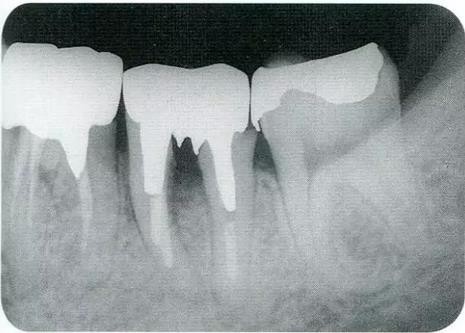

▼圖16-4

圖16-4進(jìn)行牙齒分割時(shí),如圖所示一樣,要確保分割去除的牙根邊緣不會(huì)殘留在牙槽中間骨脊。如果有邊緣殘留,會(huì)造成軟組織發(fā)紅,引發(fā)炎癥。

▼圖17

圖17 將右上6近中頰側(cè)根拔除,考慮到修復(fù)物清潔性的情況下進(jìn)行備牙。牙齒分割后如果有邊緣殘留,就會(huì)使切割面的牙齦發(fā)紅無(wú)法治愈。